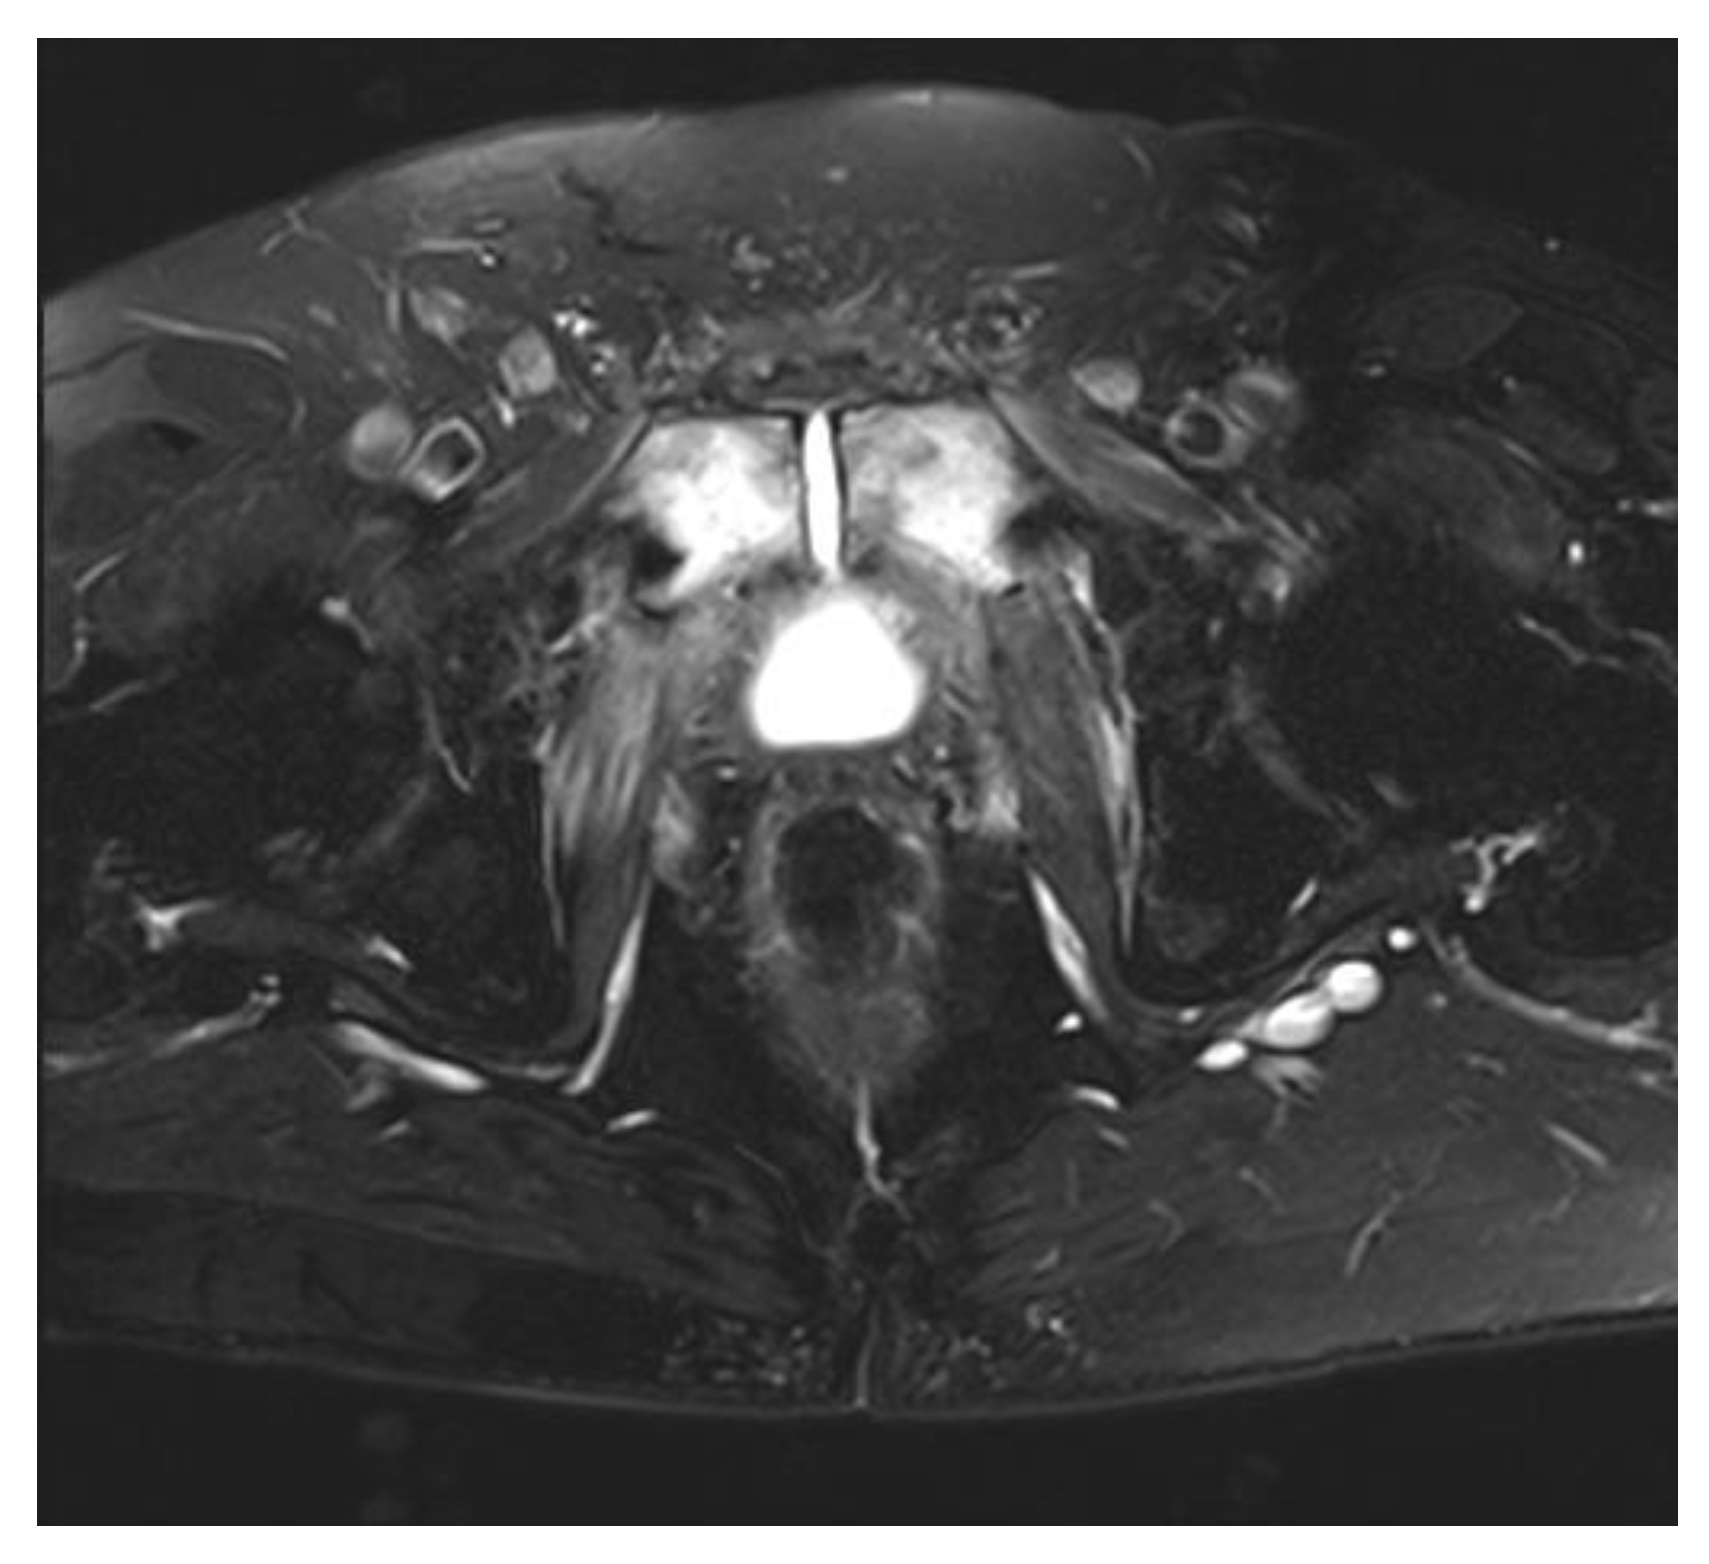

2. Pubic Osteomyelitis with Urosymphyseal Fistulae